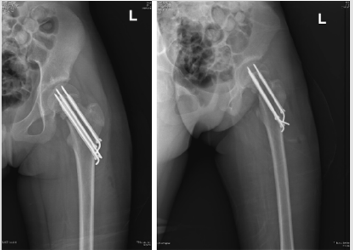

Three 0.5 cm incision was made in the lateral side, three K-wires were put into the femoral neck under monitoring by the C-arm fluoroscopy. Every K-wire’s end was 2-3 mm under the osteoepiphysis. Three cannulated screws were screwed into the femoral neck and the fracture was compressed. Three K-wires were further knocked into the femoral neck with a hammer. Every K-wire’s end was 2-3 mm under the cartilage of femoral head. Then the other ends of K-wires were bended and cut off. After washed with normal saline, the incision was stitched (Figure 2).